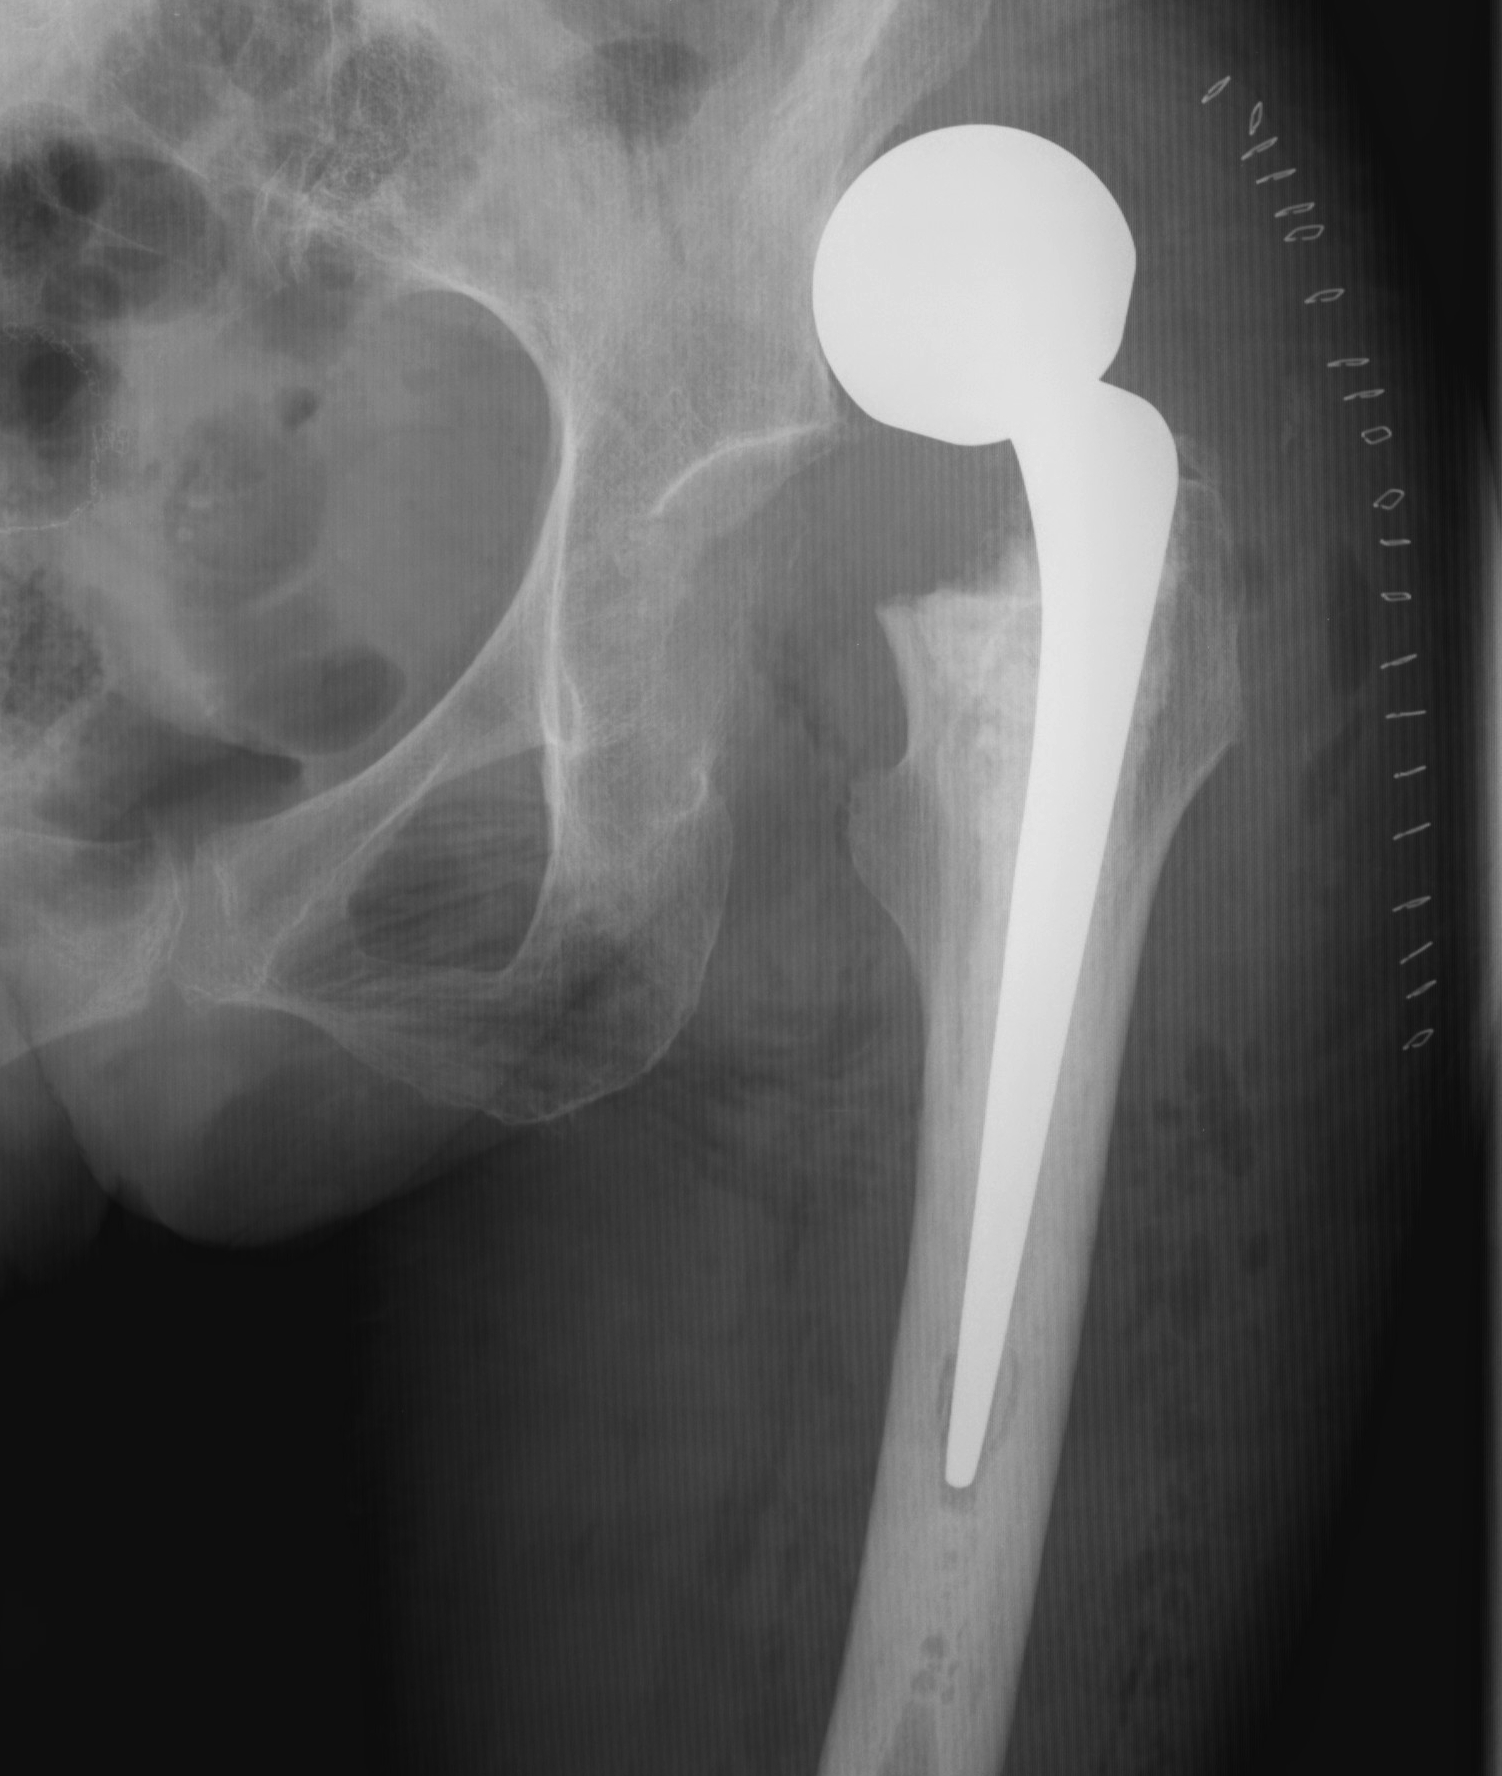

Total hip arthroplasty

Indications

Young, active, mobile patient with neck of femur fracture

Issues

THA

- better functional outcome in young mobile patient

- higher cost

- higher dislocation rates

HEALTH investigators NEJM 2019

- RCT of 1495 patients > 50 with displaced femoral neck fracture

- HA versus THA

- reoperation rate same in both groups (8%)

- dislocation: 2% HA versus 5% THA

- serious adverse events: 37% HA verus 42% THA

- modest improvement in function for THA over HA, clinically unimportant